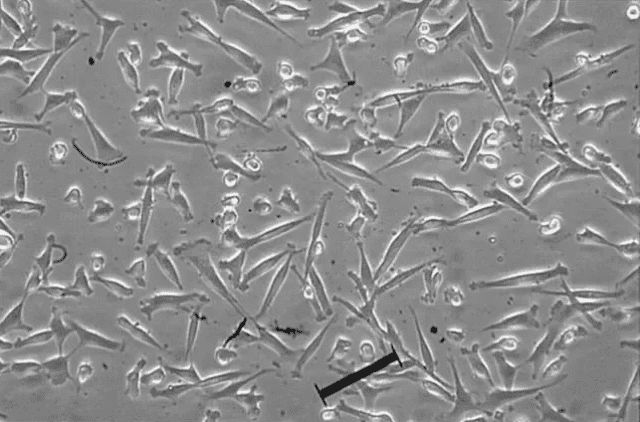

隨著人們對(duì)醫(yī)療保健意識(shí)的日益增強(qiáng),間充質(zhì)干細(xì)胞等干細(xì)胞概念已通過各種宣傳渠道引起公眾的關(guān)注。截至2022年3月,已有1400多項(xiàng)間充質(zhì)干細(xì)胞臨床試驗(yàn)在Clinical Trials中注冊(cè)。其中,我國進(jìn)···